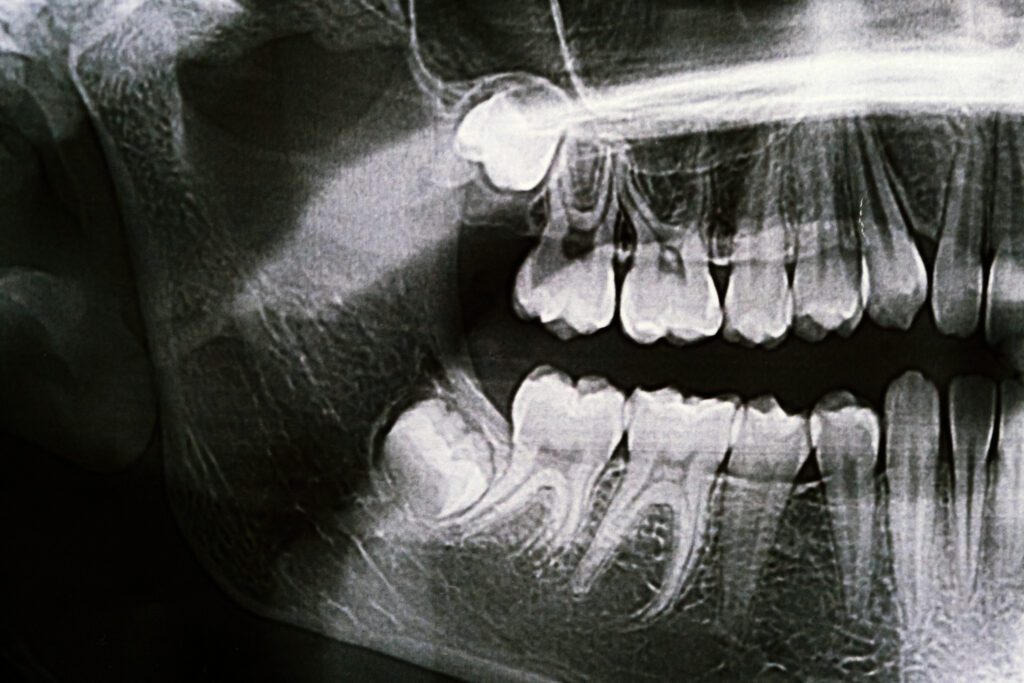

An average adult mouth is designed to hold around 28 teeth comfortably but most adults end up with 32 teeth. These additional four teeth are called wisdom teeth, (AKA) third molars. The reason that some adults grow wisdom teeth is that throughout evolutionary history the human jaw has become smaller and smaller. Because of this the wisdom teeth become blocked or impacted by the other teeth around them. This can become extremely traumatizing. If the wisdom tooth partially erupts, food can get trapped in the tissue surrounding the tooth, which can lead to bacterial growth and possibly serious infection.